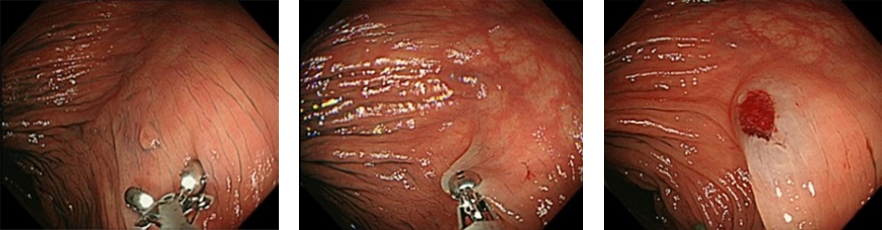

内視鏡と専用のナイフを用いて粘膜下で剥ぎ取る治療法です。大きな病変でも早期癌であれば確実に切除することが出来ます。当院では2003年より導入し多くの症例で非常に良好な成績をおさめています。食道・胃・十二指腸・大腸で治療可能です。

入院期間は8~10日で済むので、治療費も低く抑えることが出来ます。退院後も今までどおりに日常生活が可能です。